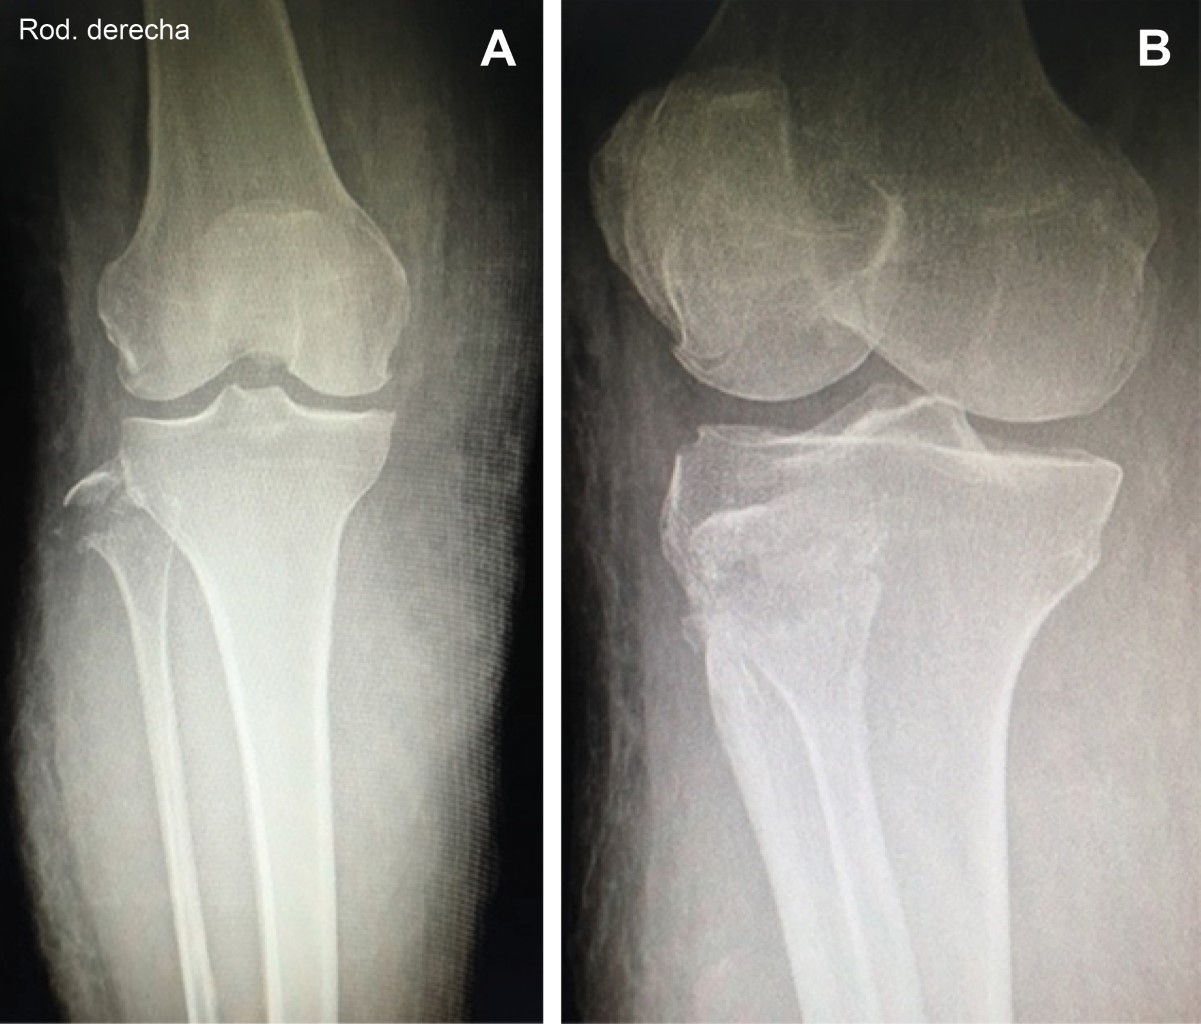

Paciente femenino de 49 años, sin antecedentes de importancia, que acude a urgencias por presentar dos horas antes de su arribo traumatismo directo sobre pierna derecha por automóvil, a la exploración: zona equimótica rodilla y cara anterointerna de pierna y tobillo, dolor intenso sobre cabeza de peroné, hipoestesia en territorio equimótico, al igual que en territorio cutáneo del nervio peroneo; sin datos de síndrome compartimental, pulsos y llenado capilar normales, con vendaje de Jones se hospitaliza y se solicitan radiografías (Figura 1) corroborando fractura de cabeza de peroné; al tercer día se presenta edema en pierna y presencia de flictenas, permaneciendo llenado capilar y pulsos presentes. Con el diagnóstico clínico de síndrome de Morel Lavallée se solicita resonancia magnética que lo confirma (Figura 2), la paciente presentó necrosis cutánea, que requirió de debridación y aseos quirúrgicos seriados, además de injerto de piel, reconstrucción del complejo posterolateral de rodilla con técnica de Larson modificado, liberación del nervio peroneo y rehabilitación prolongada.

Figura 1